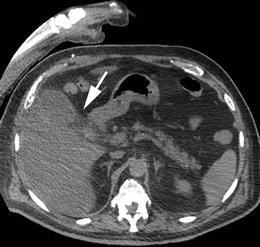

Fig. 1